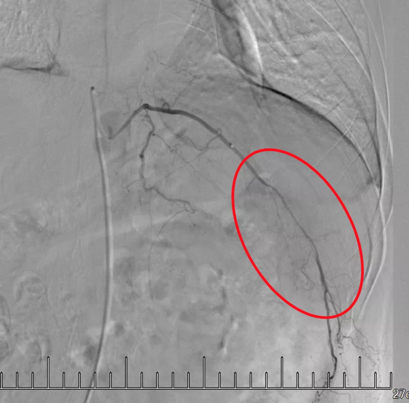

微導管插管到轉(zhuǎn)移瘤所在肋間動脈

造影顯示紅圈內(nèi)“烏云”區(qū)域為腫瘤。